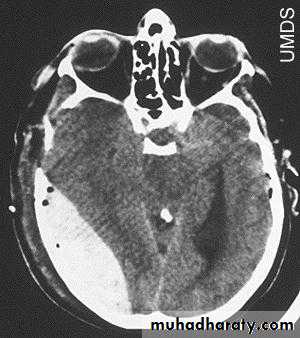

d. Subarachnoid Haemorrhage

Trauma is the commonest cause of SAH although aneurysms are the most common cause of spontaneous SAH.

Traumatic SAH is managed conservatively.

5. Hydrocephalus

a. Acutely due to obstruction of CSF outflow due to intraventricular blood.

b. Delayed post-traumatic communicating hydrocephalus due to impaired CSF reabsorption following traumatic subarachnoid haemorrhage

Intraventricular blood can lead to Hydrocephalus